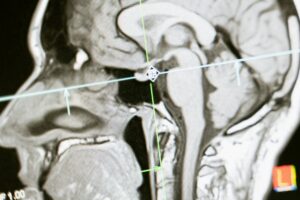

Imagem de ressonância magnética do cérebro destacando estruturas como a amígdala e o sistema límbico relacionados à ansiedade.

amigdala e sistema límbico na ansiedade

No cérebro existe uma estrutura chamada amígdala, localizada no sistema límbico. Ela é responsável por identificar sinais de ameaça.

Quando a amígdala detecta perigo, o hipotálamo ativa o eixo HPA (hipotálamo-hipófise-adrenal), estimulando a liberação de hormônios como adrenalina e cortisol.